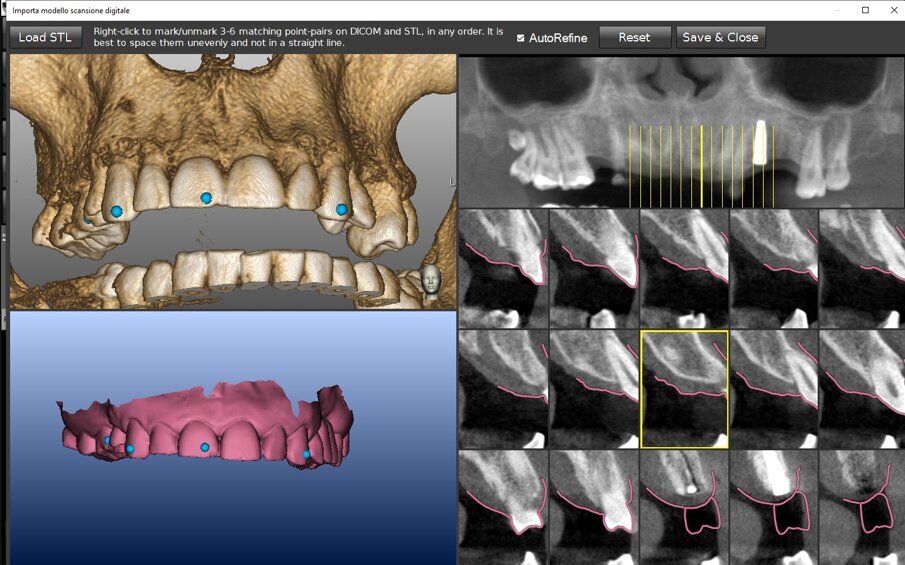

La registrazione (matching) è sempre necessaria, sia nella chirurgia guidata sia in quella navigata ma le differenze tra le due tecnologie sono già ravvisabili nell’uso che fanno di questo complesso algoritmo matematico. Nella chirurgia guidata la registrazione avviene su una media delle superfici TAC e STL del modello ed ha il compito di posizionare il modello (digitale o digitalizzato) rispetto alla TAC e, dunque, rispetto al piano di trattamento: l’errore di questo posizionamento corrisponde ad un dislocamento complessivo degli impianti durante la realizzazione clinica. Un processo protocollato, meccanizzato ed automatizzato permetterebbe di misurare questo errore e prevederlo per ciascun caso. È esperienza diffusa di ogni odontoiatra, però, che la realtà clinica, sebbene digitalizzata e protocollata, non è automatizzata; questa esperienza esita nella produzione di dispositivi la cui validità clinica non è costante ma rientra in un range che prevede, purtroppo, anche l’inaccettabilità. Nel caso della chirurgia guidata purtroppo vengono a coincidere due fattori concettualmente deleteri: l’impossibilità di verificare l’accettabilità del manufatto se non ad intervento ultimato e l’assoluta impossibilità di ripetizione della procedura chirurgica perché il fallimento spesso si associa a perdita di osso. Ciò si verifica anche in un protocollo full digital sebbene con minore frequenza e dipende dalle condizioni di lavoro assolutamente non standardizzabili. Una dima può nascondere un errore non clinicamente valutabile ma significativo. La chirurgia navigata fa uso allo stesso modo della registrazione ma esclusivamente a scopo diagnostico ed in fase di pianificazione (Figg. 3a, 3b). A scopo interventistico la chirurgia navigata richiede un’altra registrazione che si verifica in tempo reale e che ha lo scopo di posizionare i dati TAC nella realtà clinica di intervento integrandoli in un sistema di realtà aumentata on-demand (Fig. 4). Per ottenere questa sovrapposizione in tempo reale è necessaria una superficie di riferimento comune tra TAC e realtà clinica. Unica sul mercato la tecnologia navigata Navident® by Claronav® mette a disposizione ben 5 protocolli diversi per ottenere questo risultato coprendo tutto l’ampio ventaglio di realtà cliniche che ci si può ritrovare ad affrontare (pazienti totalmente edentuli, pazienti parzialmente edentuli, pazienti parzialmente edentuli ma con importanti fenomeni di scattering e beam hardening, etc.) (Figg. 5a-5f).

Figg. 3a, 3b - La registrazione di un modello con ceratura diagnostica nel software Navident® by Claronav®. a) Identificazione di punti di accoppiamento; b) integrazione finale del modello con ceratura diagnostica nel software per la pianificazione. N.B. Questo uso dell’algoritmo di registrazione è esclusivamente diagnostico in una tecnica di chirurgia navigata.